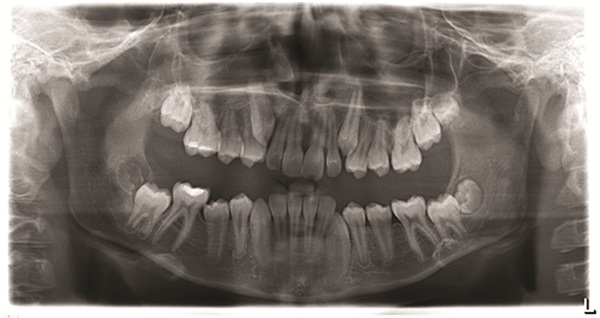

A 12-year-old male presented with severe Class II, deep bite, and significant crowding. The original poster was torn between two conflicting clinical pictures. Half the diagnostic findings pointed toward extraction: second molars impacted in the ramus, a blocked lower left canine, blocked maxillary canines, and a nearly full-step Class II relationship. The other half suggested non-extraction with vertical control to avoid deepening the bite further. The concern was that by the time crowding was resolved and the deep bite corrected, the incisors would be too flared for effective Class II correction without further proclination. The question posed to the forum was whether immediate upper first premolar and lower second premolar extractions were the best route forward (Figs. 1–11).

One contributor emphasized that this was not a surgical case and argued that fixed functional therapy offered a predictable approach through tooth movement. They viewed a Herbst as the most predictable way to distalize upper molars while acknowledging that the panoramic radiograph showed evidence of posterior mandibular crowding. Depending on the severity of that crowding, either upper first premolar and lower second premolar extractions or Herbst therapy could yield good results.